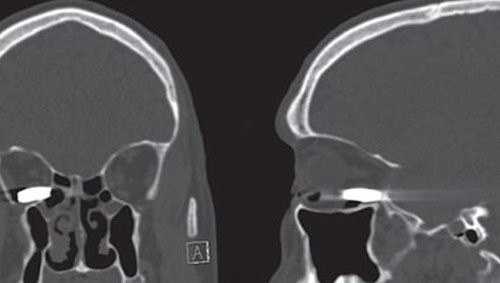

На удивительных медицинских сканах, опубликованных журналом JAMA Ophthalmology, видна пуля, которая застряла в глазнице 45-летнего мужчины. Имя этого пациента не называется, но зато описывается, что он получил огнестрельное ранение глаза из пистолета калибром в 22 мм. Обычно подобного рода выстрелы считаются смертельными, поскольку проходящая через глаз пуля разрушает мозг, но в этом случае мужчина выжил. Более того, он практически не получил ни одной царапины и даже не потерял зрения.

Пациент избежал смерти, поскольку пуля вначале прошла через дверь и замедлила скорость перед тем, как войти в глазницу. Рассказывая об этом случае, врачи из Калифорнийского университета в Сан-Франциско подчеркивают, что обычно огнестрельные ранения зависят от размера, скорости и траектории пули. Традиционные пули для огнестрельного оружия являются достаточно крупными, они движутся со значительно большей скоростью, чем пульки от пневматического оружия. Но в случае с этим мужчиной произошло настоящее чудо, аналогов которому сложно отыскать.